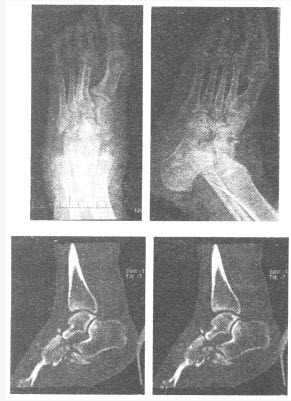

患者,女性,61岁,3年前腰椎手术史,术后开始左下肢感觉减退、麻木、无力,左足隐痛,期间无外伤史,左足拇趾曾不明原因窦道形成,后自愈,现左足持续疼痛、肿胀,加重半个月,左下肢跛行。其X线及CT图像如下,诊断左足病变为()

A:疲劳性骨折

B:退行性变

C:Charcot关节

D:撕脱性骨折

E:化脓性关节炎